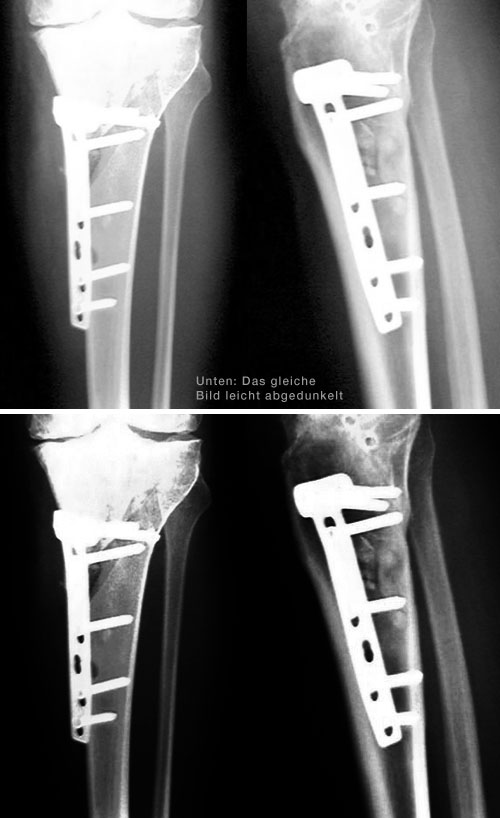

20. Mai 2005: Die Details sind bekannt

Anfang August solls so weit sein: Die Röntgenbilder zeigen, dass die Belastungsachse falsch liegt und die innere Gelenkfläche zu stark belastet ist. Hier gibts praktisch "Knochen auf Knochen". Durchgeführt wird nun eine "medial aufklappende, treppenförmige Tibia-Osteotomie", was soviel heisst wie: Schienbein unterhalb des Knies aufsägen, einen Keil rausnehmen und mit einer Platte wieder zusammenschrauben. Dies wird die Belastungsachse Richtung Mitte legen und das Gewicht besser verteilen. Dazu gibts eine Arthroskopie des Kniegelenks, bei der diverse Knochenwucherungen entfernt werden. Rund drei Monate Krücken sind angesagt. Im Vergleich zum künstlichen Kniegelenk, das mir in rund 20 Jahren blüht, Peanuts...

Montag, 19. September: Good News

Grauer Himmel, Bise, Kälte - doch die Röntgenkontrolle und Sprechstunde bei Prof. Stäubli verlief durchwegs positiv: Die Schrauben halten, die Stellung der Beine stimmt, die Gelenksachse stimmt. Nächste Kontrolle in drei Monaten - und in drei Wochen kann ich bereits die Krücken in die Ecke stellen. Das ist viel besser als erwartet.

Auch sonst ist fast alles in Butter: Schon seit zwei Wochen fühle ich, dass es möglich sein sollte, voll aufs operierte Bein zu stehen - erstaunlich für so einen komplexen Eingriff. Nun ists offiziell: Ab sofort kann ich daheim auch ohne Stöcke kurze Distanzen gehen. Medis nehme ich schon seit etwa zwei, drei Wochen keine mehr - auch das ist verglichen mit früheren Operationen erstaunlich. Strecken kann ich das Knie (zum ersten Mal seit dem Unfall im April 2001!) ganz, beugen bis etwa 110-120 Grad - in den letzten Wochen stieg dieser Wert fast täglich. Cool - alles durchwegs positiv also! Einzig ein kleiner Restschmerz im Osteotomiespalt ist noch vorhanden, dazu die üblichen kleinen Arthrose-Stiche im Knie. Bald gehts los mit deftiger Kräftigung, dann sollten die Muskeln auch schnell wieder zurück sein.

Die aktuellen Röntgenbilder (bitte klicken für grössere Fassungen):

Vergleich 15. August 2005 und 19. September 2005 von vorne

Vergleich 15. August 2005 und 19. September 2005 von der Seite